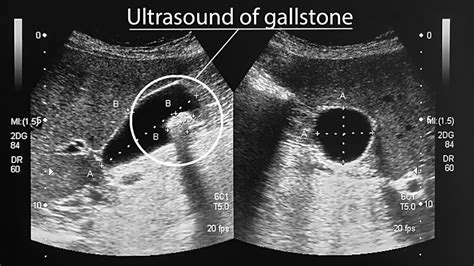

When medical professionals perform an ultrasound or a CT scan, they use specific imaging techniques to locate these deposits. In Gallbladder Stones Pictures taken from clinical settings, stones are categorized into three main types based on their composition:

Stone Type Composition Typical Appearance

Cholesterol Stones Primarily hardened cholesterol Yellow-green in color; often smooth or faceted

Pigment Stones Bilirubin Dark brown or black; usually small and numerous

Mixed Stones Combination of both Varied texture and color patterns

⚠️ Note: Diagnostic imaging such as an ultrasound is the gold standard for identifying these stones, as it captures real-time data that static photos cannot replicate.

Modern medicine relies heavily on sophisticated scans to see what is happening in the biliary tract. Unlike generic Gallbladder Stones Pictures found online, medical-grade imaging provides a precise map of the gallbladder, the bile ducts, and the presence of any blockages. An ultrasound remains the most common first-line test because it is non-invasive and does not use radiation.